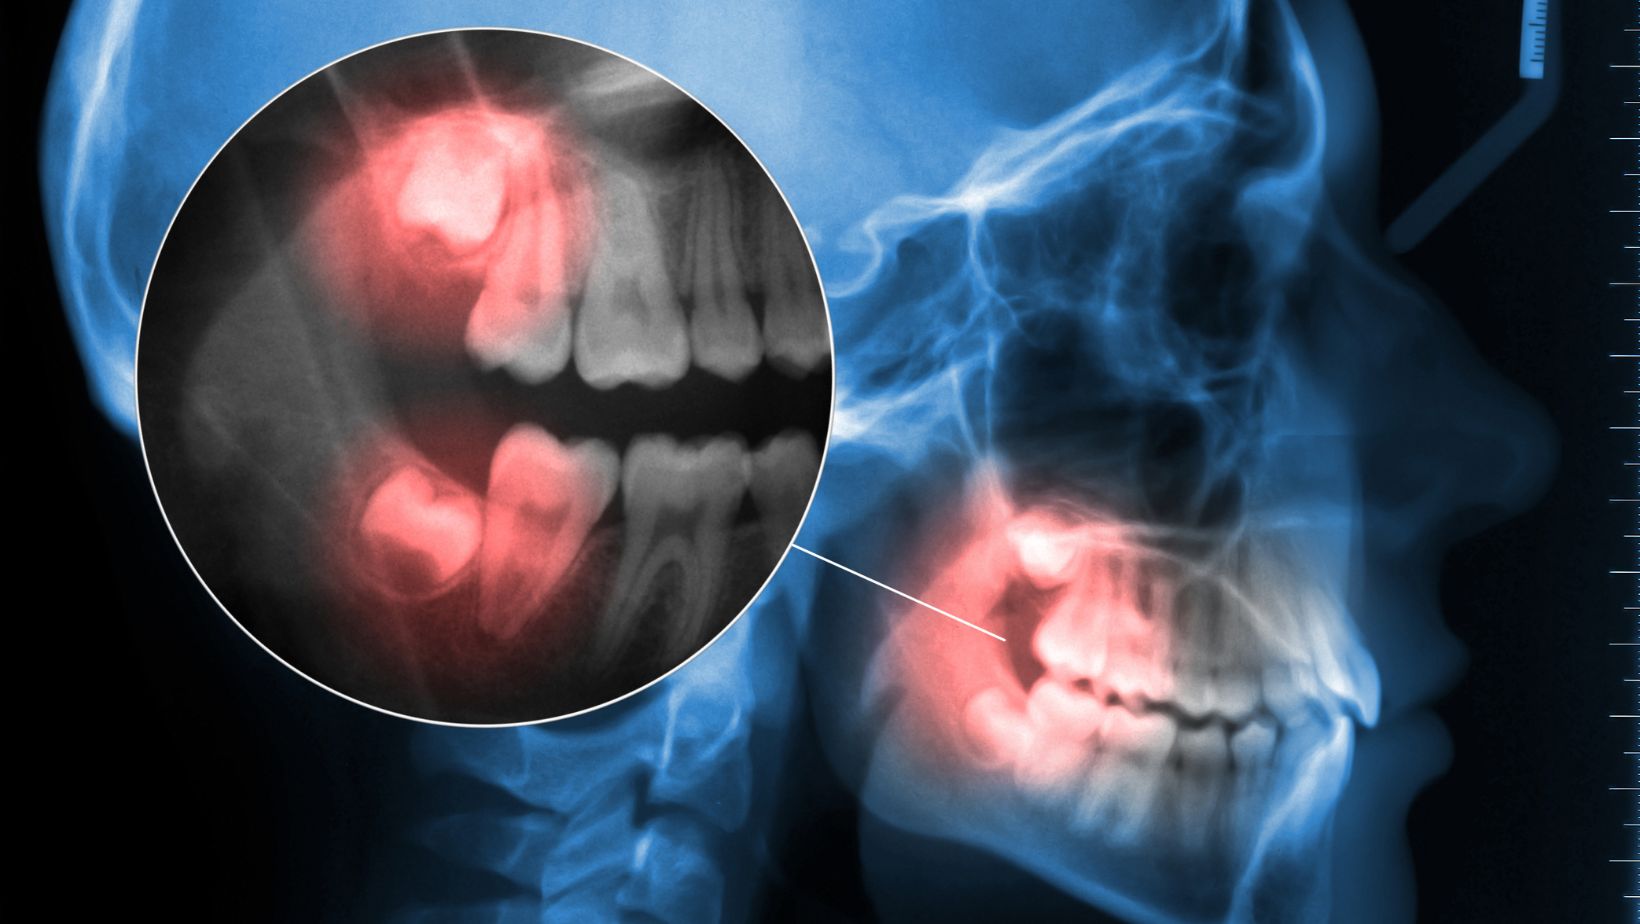

Răng khôn hay còn gọi là răng số 8 là chiếc răng mọc cuối cùng trên cung hàm. Thông thường, răng khôn mọc khi ở độ trưởng thành khoảng từ 17 đến 25 tuổi. Do mọc muộn khi xương hàm đã ổn định, khoảng trống bị hạn chế nên răng khôn dễ mọc lệch, mọc ngang, đâm vào răng số 7, hoặc chỉ trồi nhú lên một phần gây viêm nhiễm.

Chính vì vậy, mà răng khôn thường được xem là nguyên nhân gây đau nhức và các bệnh lý răng miệng phức tạp.

• Sâu răng số 7: do răng khôn tạo khe nhét thức ăn

Nếu không được điều trị sớm, răng khôn sẽ làm yếu xương hàm, gây ảnh hưởng toàn bộ hàm răng.

• Ảnh hưởng dây thần kinh

Một số ít trường hợp răng khôn mọc ngầm sát dây thần kinh hàm dưới. Nếu thực hiện bởi bác sĩ tay nghề yếu có thể gây biến chứng như: khiến bệnh nhân bị tê môi, tê cằm tạm thời hoặc liệt cơ mặt.